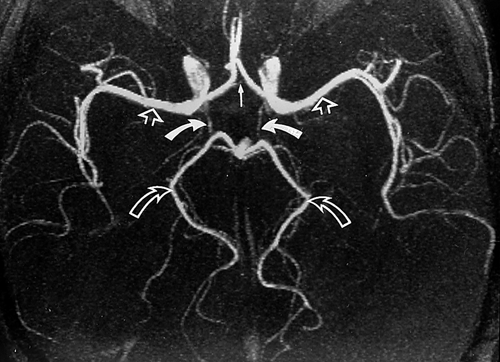

De façon physiologique, les artères communicantes postérieures ne sont pas très larges, y'a vraiment très peu de sang qui y passe (comme tu peux le voir sur ces deux angiographies) :